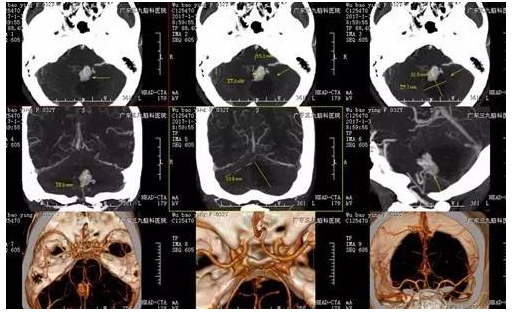

伍某某,32岁,发现颅内占位病变2年,行走不稳1天,为求进一步治疗,来我院就诊。入院后完善相关检查后,术前CTA提示实体病变,血供异常丰富,术前MR提示肿瘤位于桥臂背侧,行小脑血管母细胞瘤切除术,手术由神经外一科主任张良主刀完成,术程顺利,术后病变全切除,术后病理提示血管母细胞瘤(WHO I级),目前恢复良好。

▲术前CT